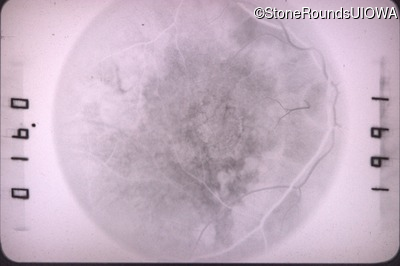

Fluorescein Angiography - Right - 20/100 -1

Exemplar